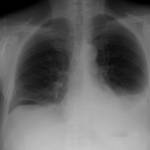

- рентгенографическое исследование органов грудной клетки – на рентгенологических снимках (их делают в двух проекциях – прямой и боковой) выявляют очаги усиления легочного рисунка, уплотнение тканей в перибронхиальной области (вокруг бронхов), при скоплении экссудата в плевральной полости – горизонтальный уровень жидкости;

- рентгеноскопия органов грудной клетки – при этом их осмотр проводят в режиме реального времени на экране рентгенологической установки. Помимо изменений, выявляемых во время рентгенографии, метод позволяет оценить способность легких к расправлению – при застойных явлениях она снижена;